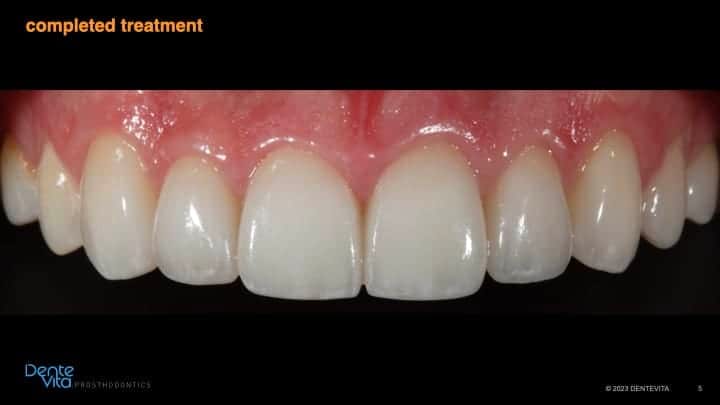

After completion of successful orthodontic therapy, missing tooth structure was rehabilitated/restored with conservative 360 degree and three-quarter porcelain veneer therapy, along with posterior occlusal partial coverage onlay restorations.

Photos of the patients original smile taken prior to the damage caused from erosion/wear were utilized to help design correct tooth form, dimensions and color characteristics of the definitive aesthetic and functional restorations.